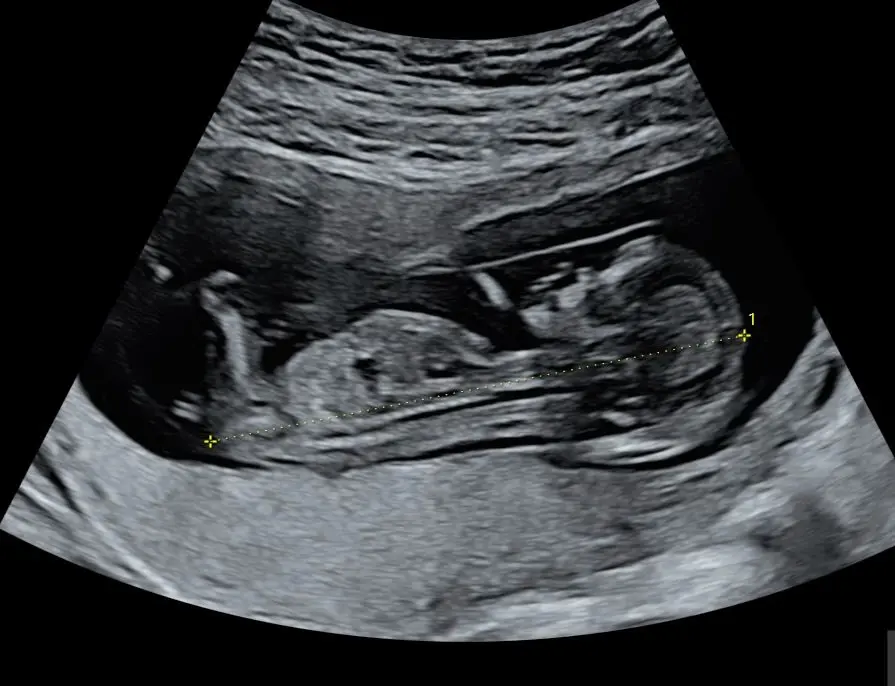

A fetal morphology ultrasound, also known as the 20-week scan or anatomy scan, is a detailed ultrasound examination that looks closely at your baby’s development and checks for any abnormalities. It is a detailed check of your baby from head to toe and is usually performed between 18 and 22 weeks of pregnancy.

This scan provides vital information about your baby’s health and development. It allows your healthcare provider to:

- Check the baby’s size and growth

- Examine the structure of the baby’s organs (such as the brain, heart, kidneys, spine, and limbs)

- Look at the placenta, amniotic fluid, and umbilical cord

- Confirm the position of the baby and placenta

- Assess for physical abnormalities or birth defects

- (If you wish) determine the baby’s sex

The procedure is performed using a transducer on your abdomen. It is a safe and non-invasive test that uses sound waves, not radiation, and poses no known risks to you or your baby. The scan typically takes around 45 to 60 minutes, but this may vary depending on the baby’s position and movement. Sometimes, if the baby is not in an ideal position to view certain structures, a follow-up scan may be scheduled.